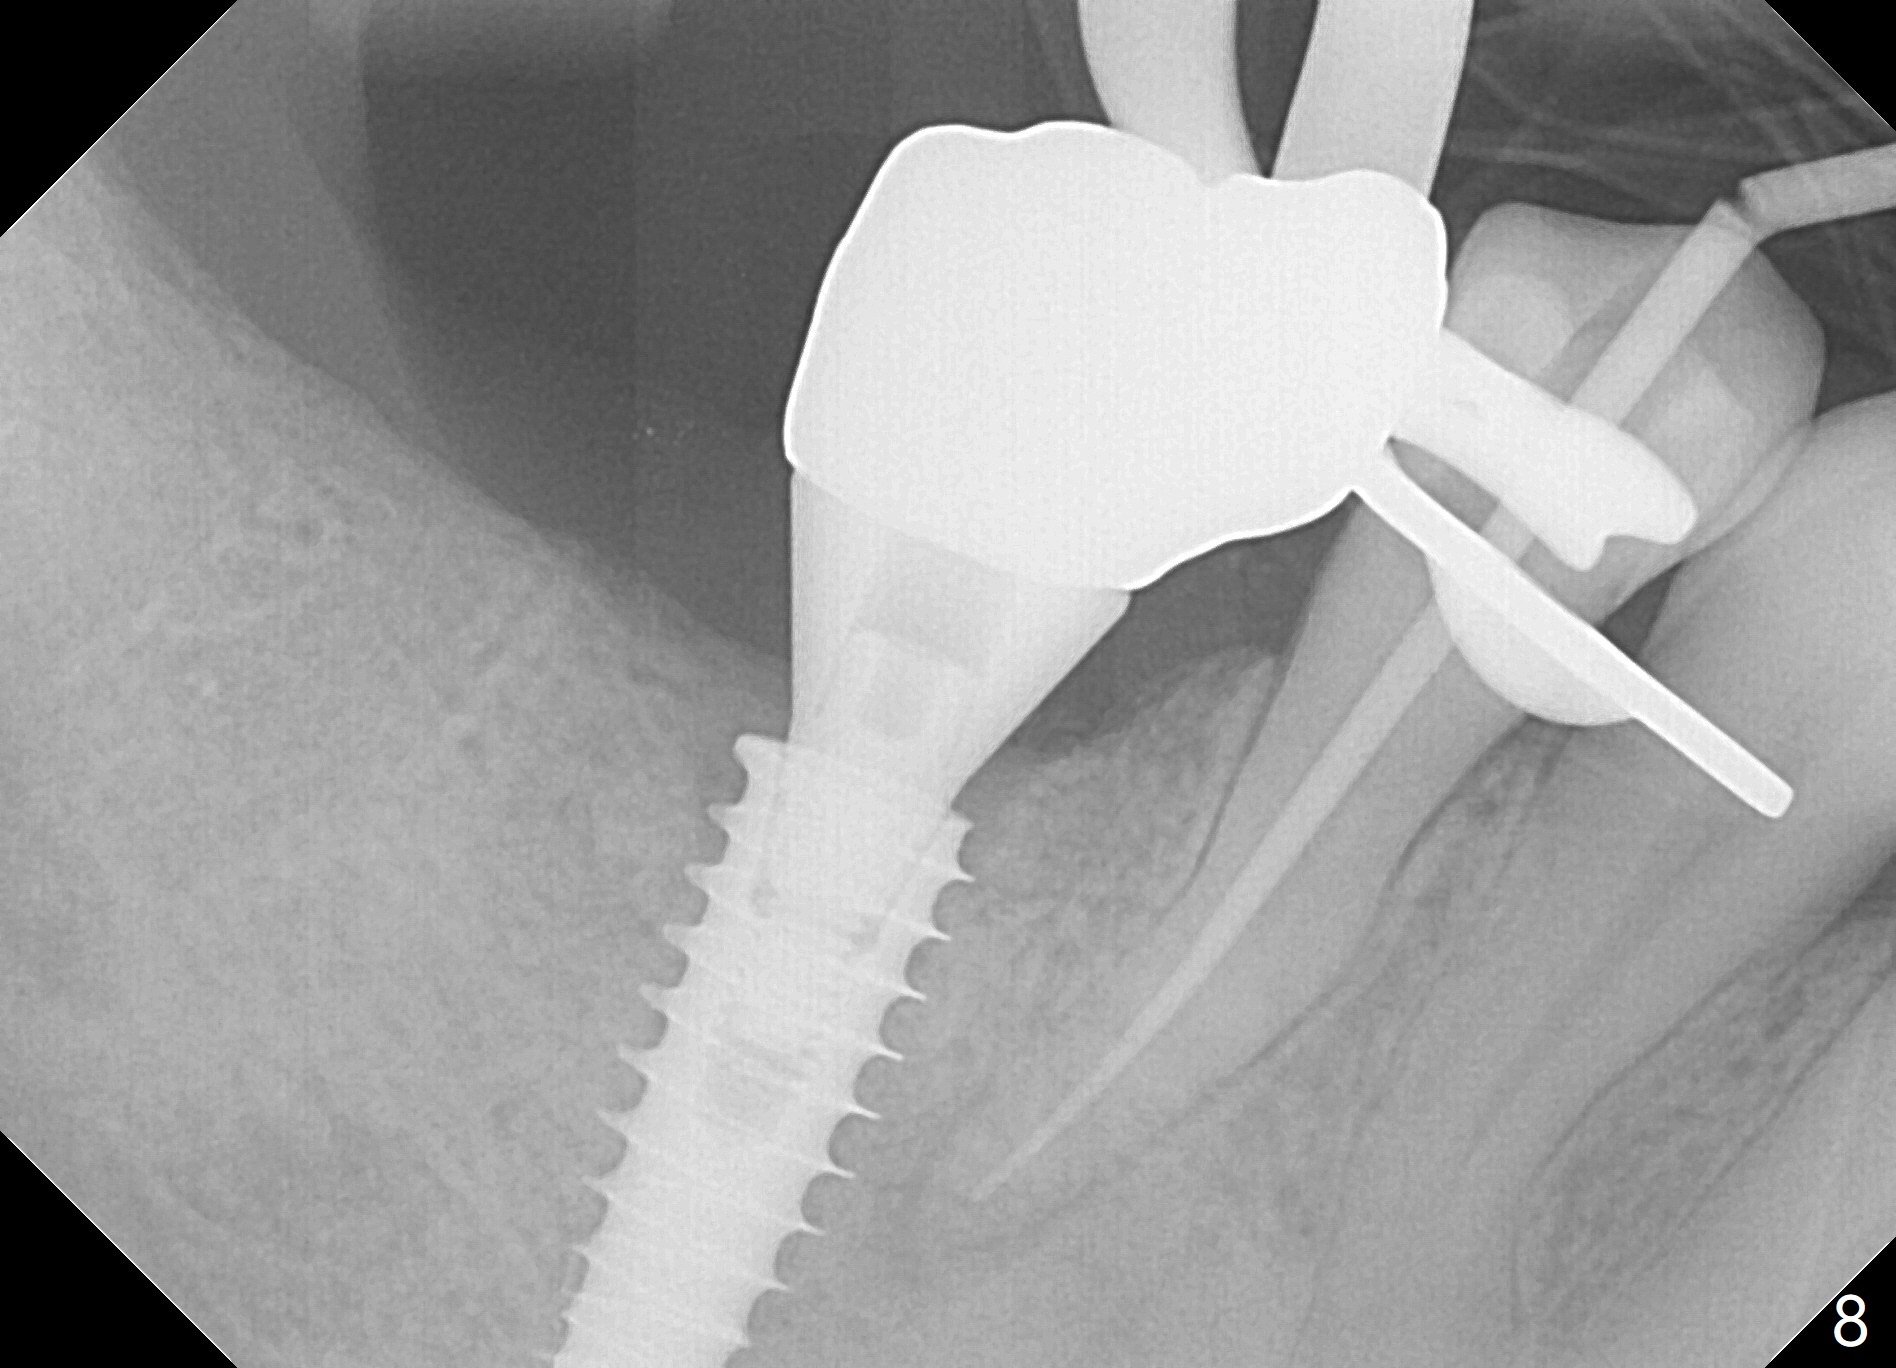

Bone graft seems to sink down and becomes denser 3 months postop (Fig.6 arrow). The bone continues being denser 5 months postop (Fig.7). There is periapical radiolucency of the tooth #29 (^). RCT is done (Fig.8). The pain persists 2 weeks postop (Fig.9,10). There is no missing canal (Fig.9). The apex is close to the implant (Fig.9 *). Apicoectomy will be performed if needed. It appears that the implant is also placed buccal (Fig.10 <) and/or the implant too large for the site. Therefore there should be a 2-3 mm buccal gap before and after implant placement. Separation and reflection of the buccal flap allows better visibility. The pain persists 1 month post RCT and 6 months post implant placement. RCT retreatment is initiated (Fig.11,12) with placement of Calcium Hydroxide paste after redebridement with 30/.04 rotary file at 23.5 mm (.5 mm longer than the earlier RCT, Fig.13). RCT retreatment finishes with apparent transportation and extrusion in 4 weeks (Fig.14,15), followed by apicoetomy (Fig.16,17) (20 days later)). Discomfort remains 2.5 months postop (Fig.18). Keep watching.